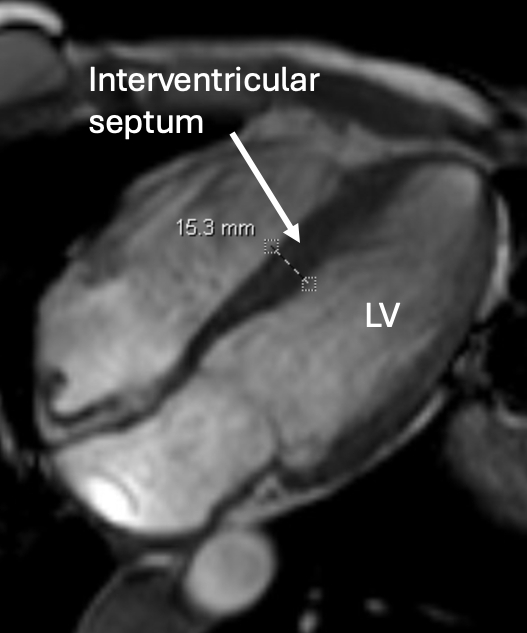

A 44-year-old female with CMT was referred to the department of genetics due to a family history of CMT. Genetic testing revealed a pathogenic variant in BAG3, specified c.1408C>T; this result prompted a referral to cardiogenomics clinic. During her cardiac evaluation, she reported a year-long history of palpitations, fatigue, orthopnea, and near-syncope. Echocardiography showed a left ventricular outflow tract (LVOT) gradient of 42 mmHg with Valsalva and asymmetric hypertrophy of the mid to apical left ventricular cavity. Cardiac MRI confirmed asymmetric HCM with thickening of the basal and mid interventricular septum and anterior segments of the myocardial wall, up to 19 mm, and mild LVOT flow acceleration. She was initiated on a cardiac myosin inhibitor for obstructive HCM, and after one year, her LVOT gradient decreased to 13 mmHg. At 1-year follow-up, she was feeling well with rare palpitations and fatigue.